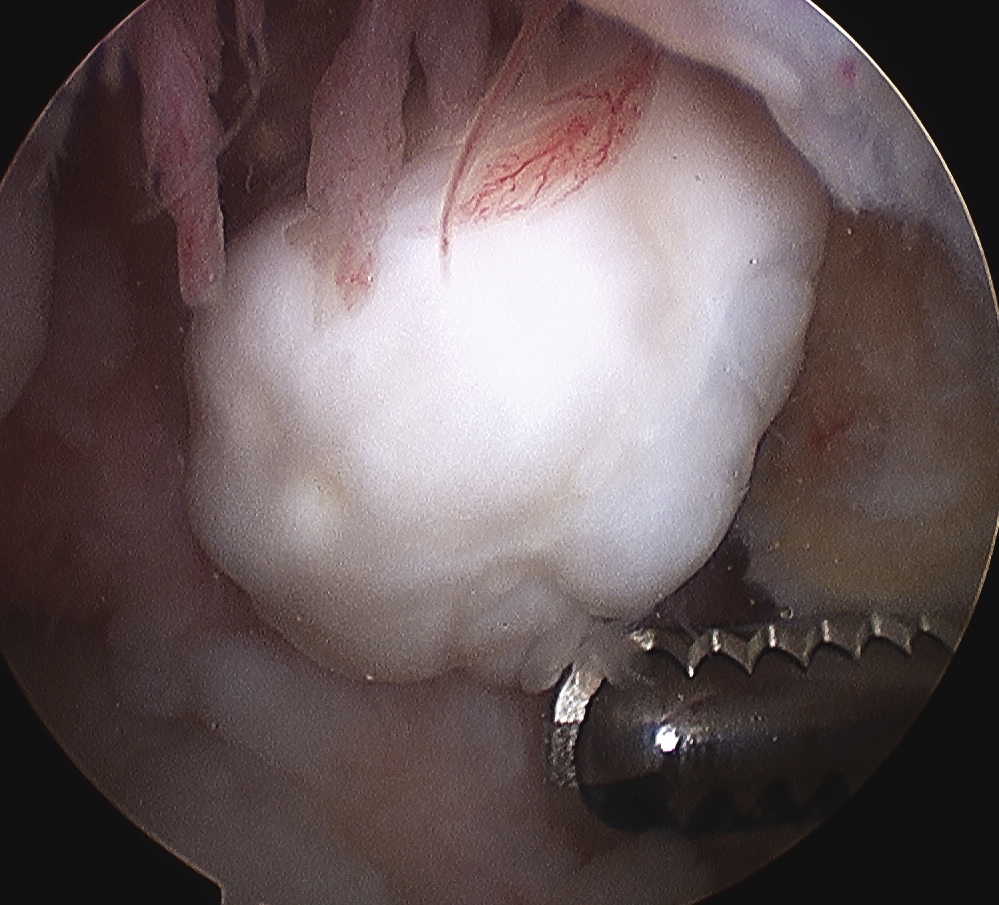

Arthroscopy

Need to look carefully

Common Sites are

1. Notch

- can be covered by soft tissue

5. Loose body can be adhered and covered in synovium